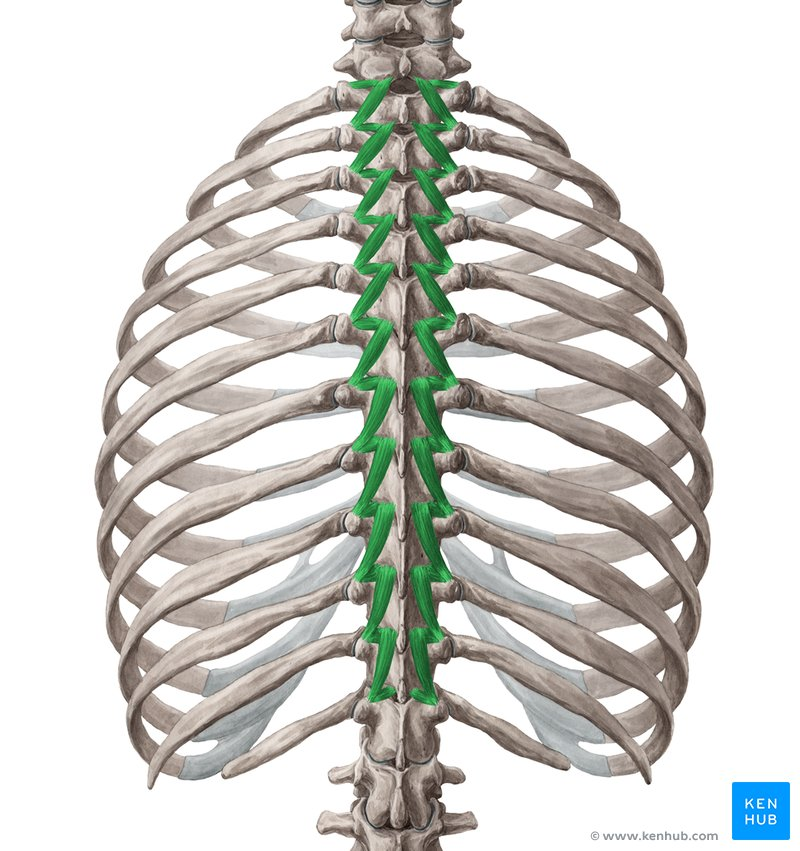

m semispinalis (thoracis)

mm multifidi

mm rotatores